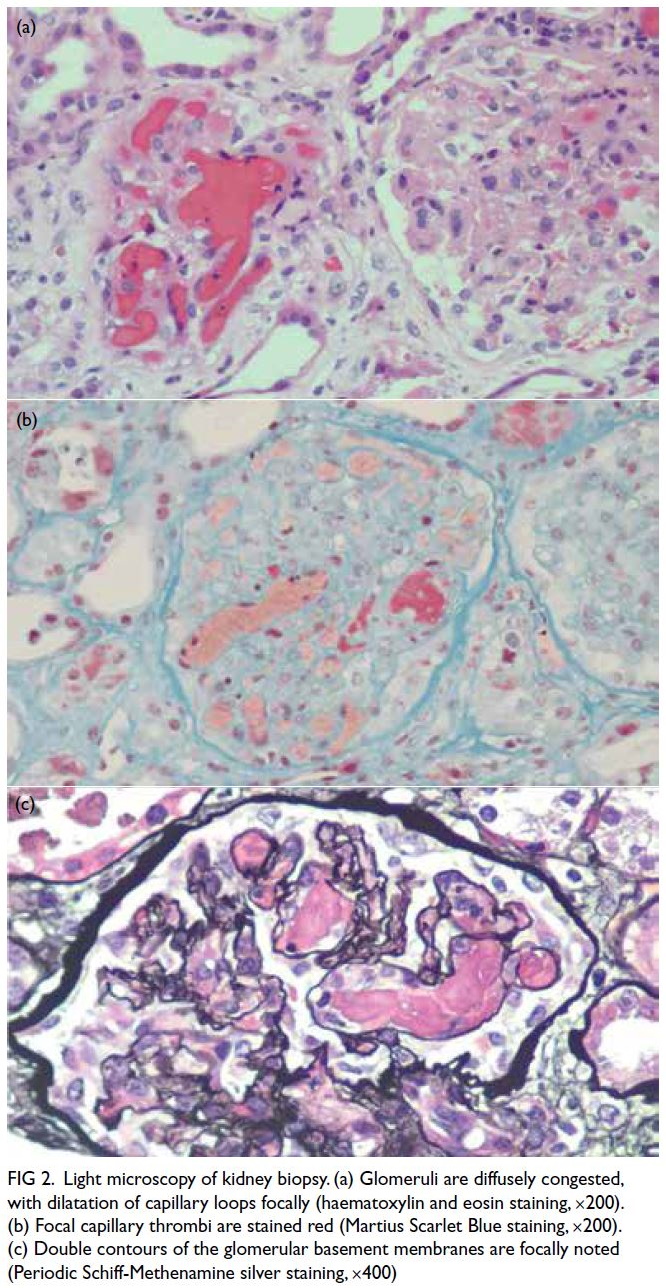

anaemia. Kidney biopsy confirmed thrombotic

microangiopathy (TMA) with congested glomeruli,

double contours, and capillary thrombi on fibrin

staining (Fig 2).

Figure 2. Light microscopy of kidney biopsy. (a) Glomeruli are diffusely congested, with dilatation of capillary loops focally (haematoxylin and eosin staining, ×200). (b) Focal capillary thrombi are stained red (Martius Scarlet Blue staining, ×200). (c) Double contours of the glomerular basement membranes are focally noted (Periodic Schiff-Methenamine silver staining, ×400)